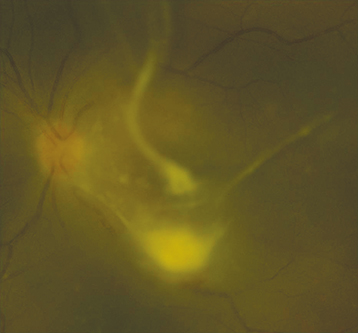

(See Figure 12.18.1.)

Discrete, multifocal, yellow-white, choroidal to chorioretinal fluffy lesions from one to several disc diameters in size. With time, the lesions increase in size, break into the vitreous, and appear as a string of pearls, especially in the case of Candida. Aspergillus has a predisposition for the subretinal space.

Vitreous cell and haze, vitreous abscesses, retinal hemorrhages with or without pale centers, AC cells, and hypopyon. A retinal detachment may develop.